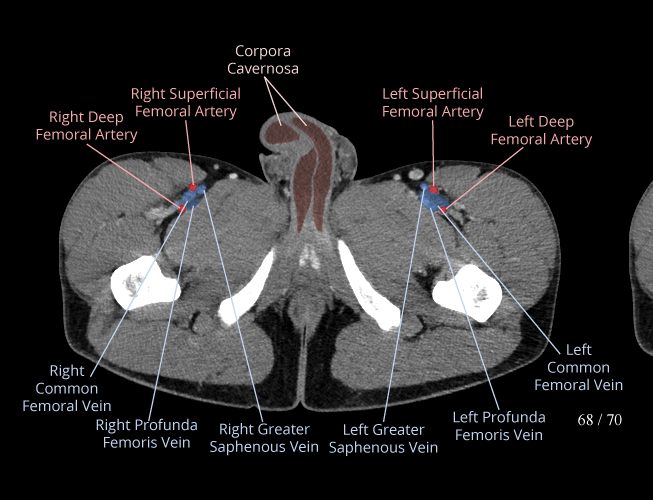

Pelvis